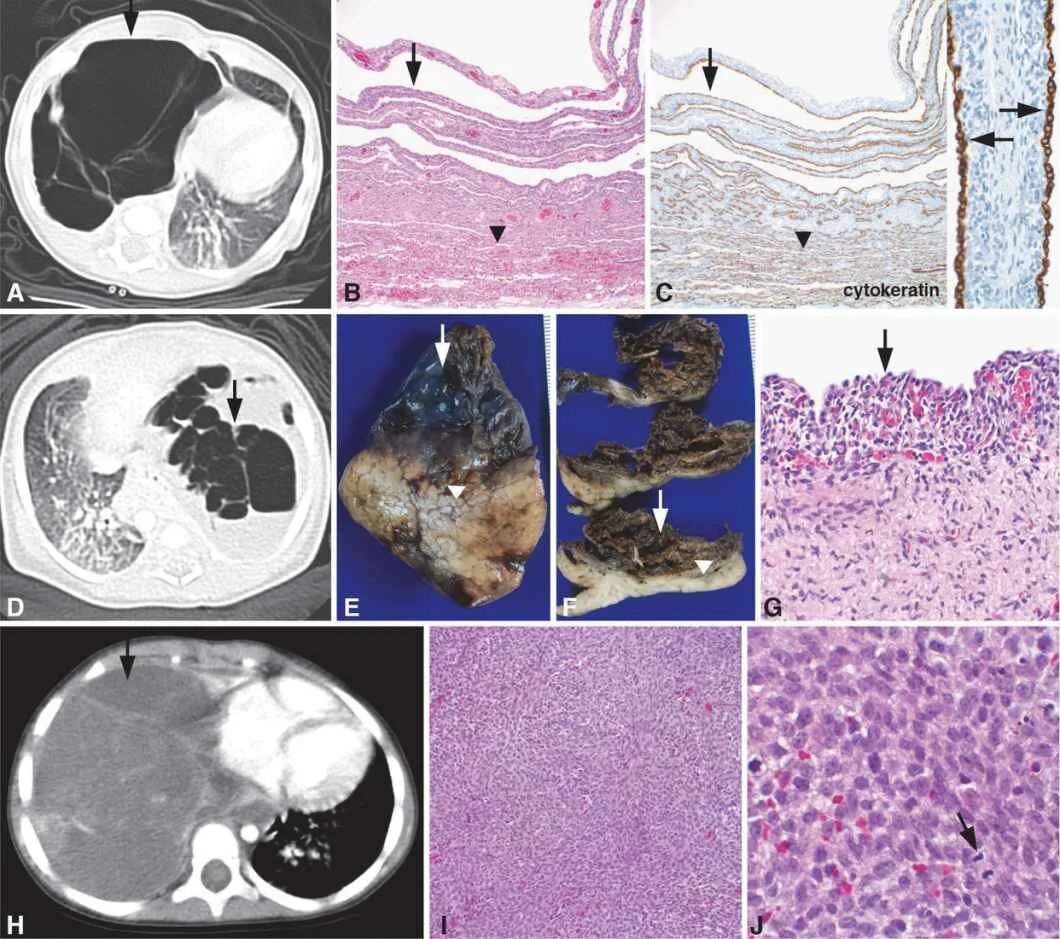

Бластома мозга